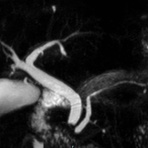

- Gallenwegssystem

- Nichtinvasive Darstellung der Gallenwege (MRCP)

- Abklärung der Ursache einer Gallenabflussbehinderung (Tumor, Gallensteine, Entzündung)